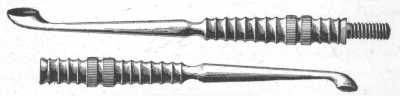

Fig. 9.

Comedo Extractor.